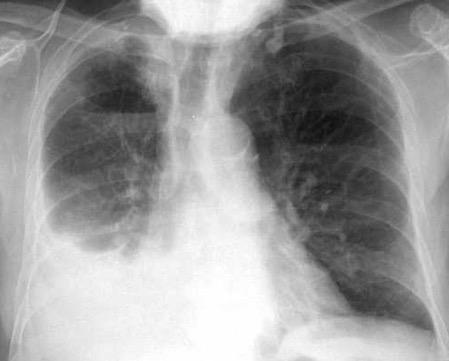

Neumonía a neumococos base izda. con derrame que aumenta.

Broncograma en lateral y en US.

(36-66% en ingresados)